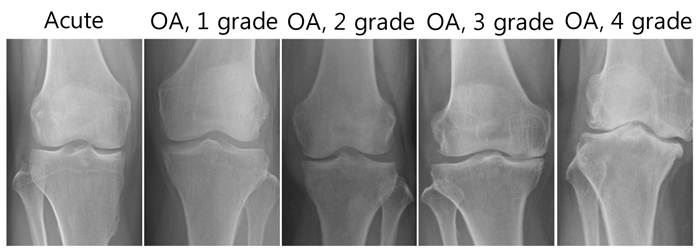

Among a total of 38 OA patients enrolled in this study, there were 33 females and 5 males (Table 1). The mean age was approximately 57.6 years and the mean disease duration was 4.63 years. Knee OA was diagnosed by clinical and radiological evaluations and divided into four groups according to the severity of OA based on the Kellgren-Lawrence radiographic grading scale, which emphasizes joint space narrowing and significance of osteophytes (grades 1 - 4, with 1 being early stage of OA and 4 severe OA). As OA progresses, the medial compartment becomes narrower and the lateral compartment becomes wider. There are also a number of osteophytes and large subchrondral cysts where the bones rubbed together. Early stages of OA are easy to distinguish from late stages of OA through X-rays (Fig. 2). However, differentiation between early stage OA and acute inflammatory conditions of the knee joint only through radiological evaluation is difficult. In fact, based on the radiologic findings, all 38 patients were initially diagnosed as OA combined with variable amounts of joint effusion. However, through further laboratory and diagnostic imaging studies, including MRI, 5 patients were finally diagnosed with acute inflammatory conditions of the knee joint, which can be combined with joint effusion.

Figure 2

X-ray data from patients with OA (grades 1 - 4) and acute inflammatory conditions of the knee joints.